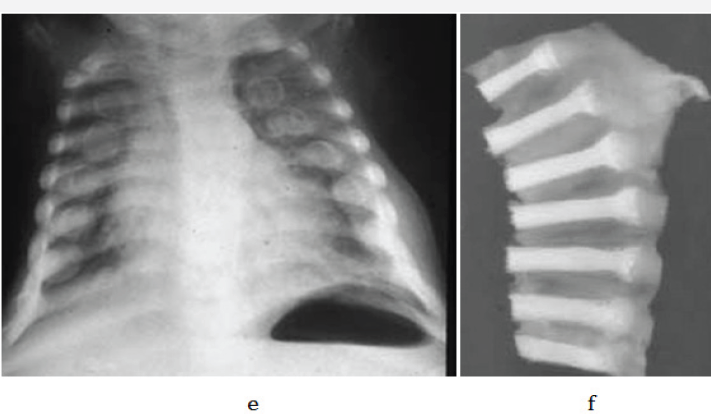

Figure 2 e & f: Rachitic rosary, a- chest, b- specimen of ribs.

In young children and adolescents, characteristic radiological appearances are noted on conventional films. These include osteoporosis, metaphyseal cupping and ground glass appearance of growing and weight bearing bones (Figure 2a-2d). Rachitic rosary deformity is common in the chest with cupping of the costochondral junctions (Figure 2e & 2f).